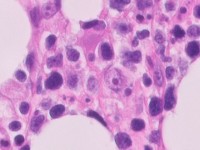

PA subcutaneous panniculitis-like T-cell lymphoma PA subcutaneous panniculitis-like T-cell lymphoma

histologisch beeld histologisch beeld

PA-foto's: dr. E.J. Kooi, patholoog, Afdeling Pathologie, Amsterdam UMC.